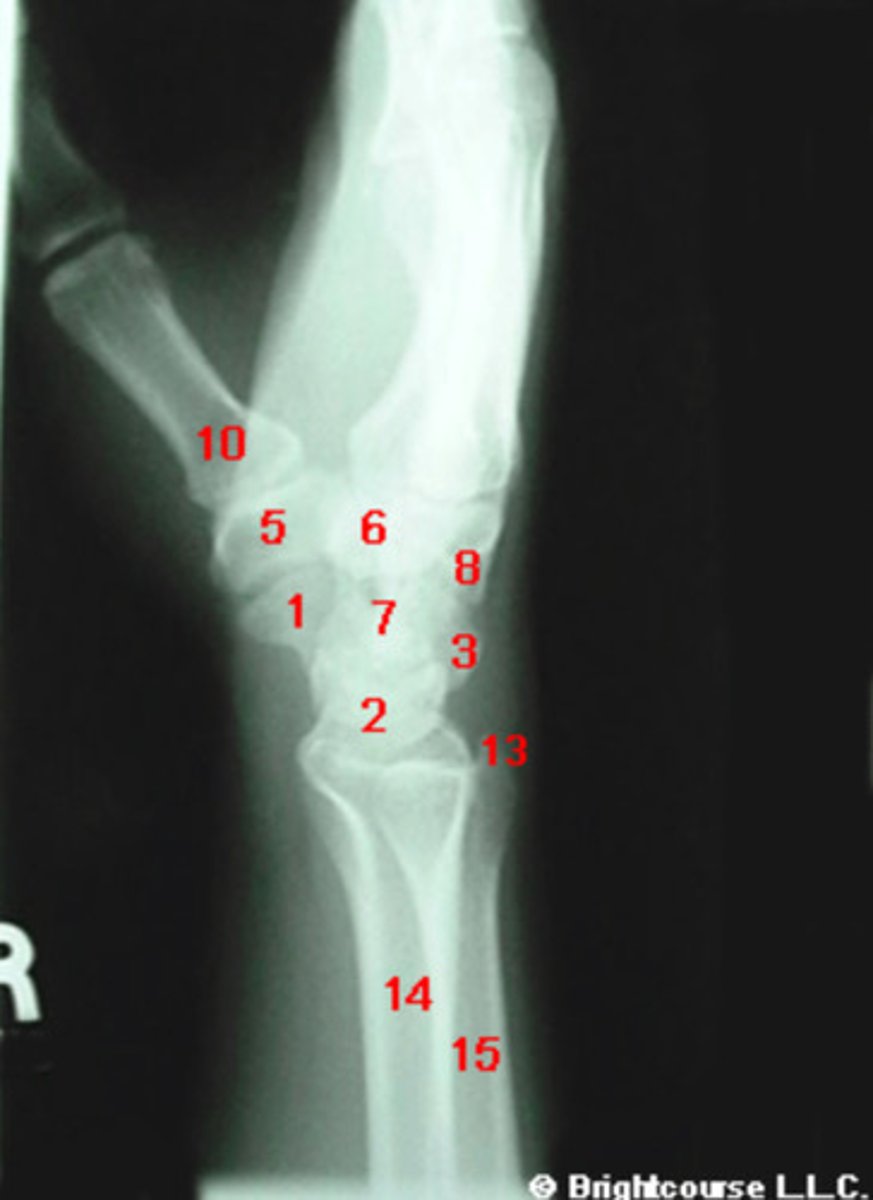

PA, internal oblique, and lateral

What are the standard plain film radiographic projections for the wrist?

Capitate

What structure is indicated by number 7?

Scaphoid

What structure is indicated by number 1?

What structure is indicated by number 2?

What structure is indicated by number 3?

What structure is indicated by number 5?

What structure is indicated by number 6?

What structure is indicated by number 8?

What structure is indicated by number 13?